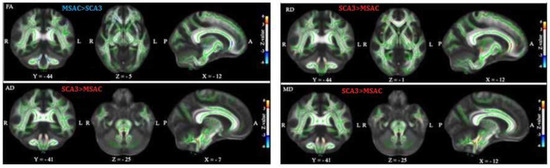

3.2. Patients with SCA3 Demonstrated Significant Decrease in FA and Increases in RD, AD, and MD